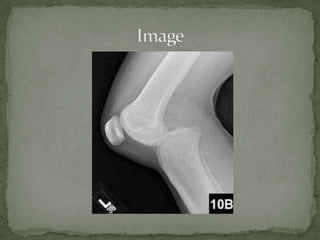

Posterior Knee Dislocation

 37 yofemale p/w knee pain s/p front-end MVC as a restrained passenger with the left knee striking the dashboard. Pt cannot move knee secondary to pain. No other injuries noted.  T 98.7 P 103 BP 117/62 O2      100% Gen: CV: Tachycardic, RR, no m/r/g Pulm: Lungs CTA bilat GU: nml Ext: Left knee grossly unstable and unable to extended. Decreased sensation over lateral foot.

 25% kneedislocations  Both Cruciate Ligament disruption (ACL & PCL)  Popliteal artery injury  Behind the lateral meniscus, posterior to Tibial Plateau  Less common than anterior dislocation as extensor mechanisms provide protection from anterior  Nerve Injury (16-40%)  Tibial and Fibular nerve 2/2 traction